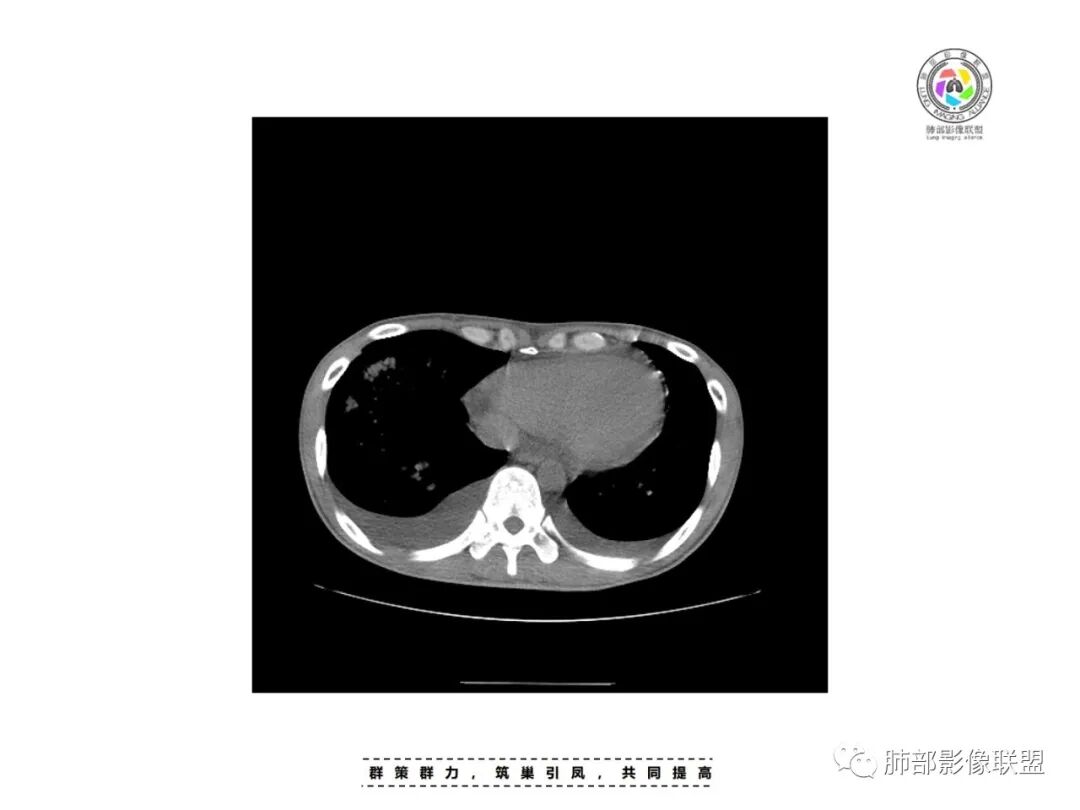

穿越七海的风:右侧胸腔积液,右肺多发斑片浸润影,内见支气管,血象白系血小板减少,LDH升高,未成熟粒细胞升高,考虑血液系统疾病,淋巴瘤或白血病

红星:病史资料:患者男,30岁,因“双小腿及双踝双足浮肿1周”入院。患者1周前无明显诱因下感双小腿及双踝双足浮肿,胸部CT示:两肺多发感染。尿酸增高,肝功能损害,两肺多发的结节状及片状的模糊阴影,小叶中心分布为主,病灶中心密度比较高,周围密度较淡,晕征,整体病灶比较单一,以渗出为主,两下肺分布,尤其是右下肺分布为甚,两侧胸腔积液,心包积液。心脏左心室明显增大。考虑肺部感染或者是血管炎的一些病变。个人认为,左心功能不全合并有肺水肿或者是血管炎的一些病变。

一切∮随缘:右肺多发大片状实变影,边界模糊,周围可见磨玻璃影,部分可见支气管穿行,支气管壁增厚,支气管扩张,血管束增粗,双肺多发结节,结节分布,以支气管束分布为主,双侧胸腔积液,心包积液,心包密度减低(贫血?),年轻男性,有下肢浮肿,实验室有血象及蛋白减低,考虑:1:病毒性肺炎2:GPA3:淋巴瘤

双侧胸水

心包积液

出血有可能,还要考虑到肺水肿,因为有胸腔和心包积液,小叶间隔也增厚。